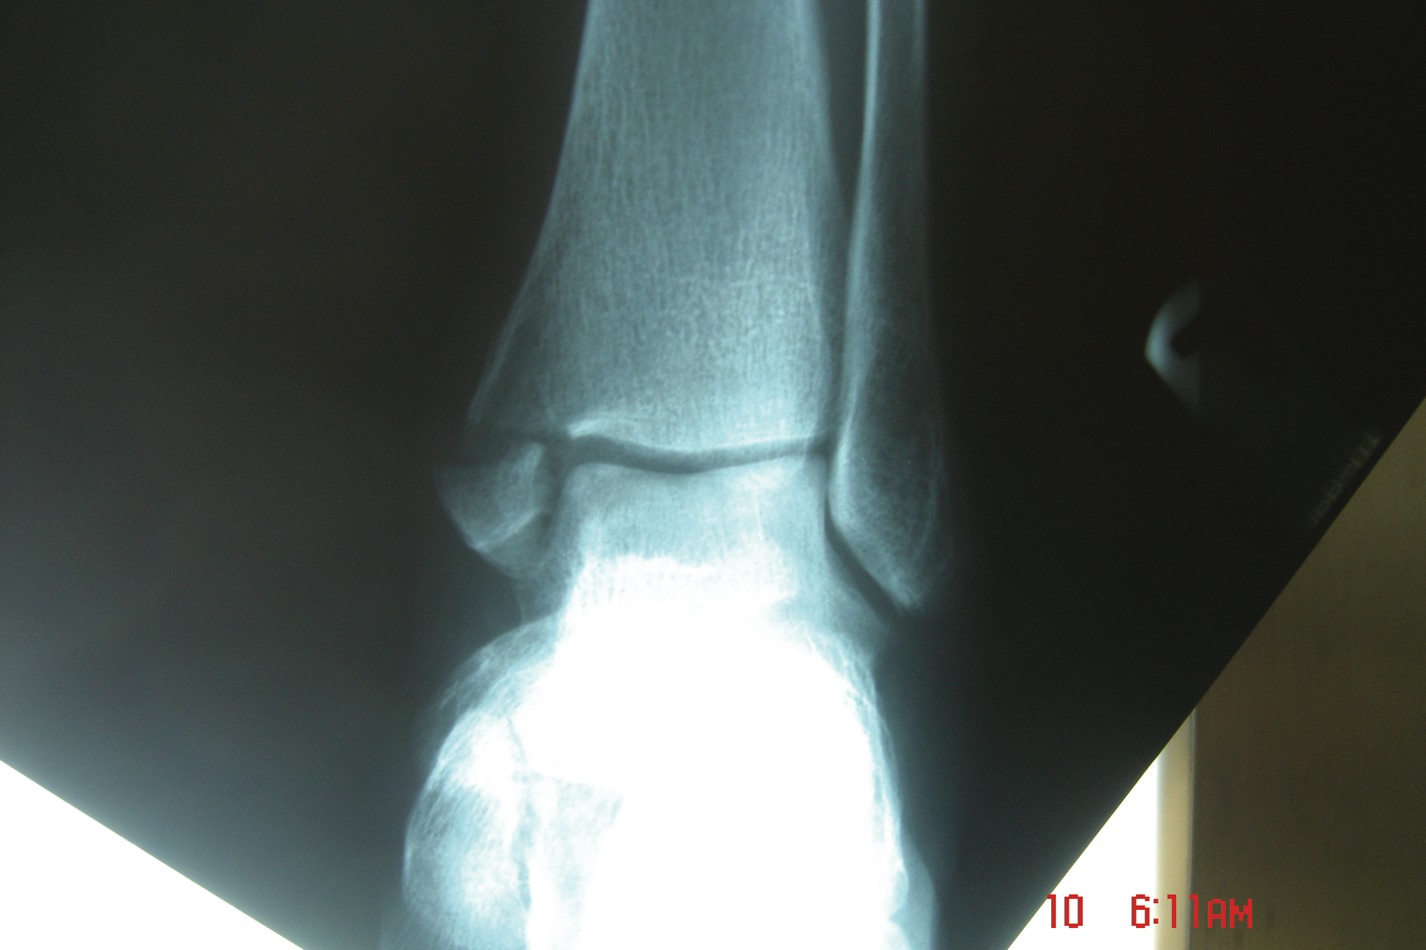

The Lauge-Hansen classification system is the most widely used system to assess ankle fractures.6 This system helps the physician visualize the mechanism of injury, the ability to reproduce the fracture, ascertain the anatomy involved and ability to reduce the fracture. (See “What You Should Know About The Lauge-Hansen Classification System” below.) This classification system was solely based on experimental cadaveric studies and clinical experiences with common fractures. The first term describes the position of the foot at the time of injury while the second term describes the direction of the pathologic force on the talus. The staging in this classification is as follows: supination-adduction, supination-eversion (supination–external rotation), pronation-abduction, pronation-eversion (pronation-external rotation).6 The Danis-Weber classification system is the second commonly utilized system among surgeons when it comes to identifying the degree of ankle fractures. However, the use of this system has increased in recent years due to the ease of classifying the fracture. The basis of this system is classified on the fracture pattern of the fibula and the integrity of the syndesmosis. This classification recognizes Type A, Type B and Type C fractures.6 With a Type A fracture, the fracture line is below the ankle joint level. These fractures account for 14.8 to 27 percent of all ankle fractures. Approximately 41 percent of ankle fractures are Type B fractures, in which the fracture line is at the level of the ankle joint. Type C fractures, which involve a fracture line below the level of the ankle joint, comprise about 20 percent of ankle fractures. The Berndt and Harty classification is the most commonly accepted system clinicians use for describing transchondral lesions. The defect often results from a shearing of the distal tibia and talar dome under compression that is often secondary to an ankle sprain or fracture. These types of injuries are difficult to recognize in acute phase due to the similar presentation of an ankle sprain. According to the Berndt and Harty classification, a stage 1 lesion is a trabecular compression fracture of subchondral bone; a stage 2 lesion is a partially detached osteochondral fragment; a stage 3 lesion involves a completely detached, non-displaced fragment; and a stage 4 lesion involves a detached and displaced fragment. In regard to assessing the degree of epiphyseal fractures in pediatric patients, the classification system proposed by Salter and Harris is the most widely accepted (see “A Closer Look At The Salter-Harris Classification System For Epiphyseal Fractures” below). The mean age for most physeal fractures is reportedly in the range of 1 to 16 years old with 10 years of age being the average.

All athletes, regardless of the level of performance, will need the appropriate physical therapy modalities and rehabilitative techniques to complete functional recovery from an ankle fracture. Athletes who are at the competitive amateur level or professional level will need to return to their performance level sooner than the weekend warrior. Athletes whose career is based on their performance and return to competition will need complete rehabilitation. These individuals have no financial constraints as compared to some amateur athletes and recreational athletes. There are three phases of rehabilitation: the acute phase, the recovery phase and the functional phase. Phase one is the reduction of pain, inflammation and edema while retarding muscle atrophy of the lower extremity complex. Improving range of motion is also a major component in this acute phase. Phase two involves improving range of motion, improving lower extremity strength, increasing neuromuscular control and regaining normal arthrokinematics (defined as function of the joint) in single planes and triplanar motion of the ankle. Phase three involves increasing power of the lower extremity complex, increasing neuromuscular control in multiple planes of motion and utilizing sport-specific training for a full return to sport.30,31 A consideration with treating athletes is that if the athlete is inactive after his or her injury, the athlete loses training adaptation. This means the athlete will “detrain” as the individual’s physiological function reverts to the normal untrained state.32 It is most essential that the athlete remain active in some form of alternative exercise or maintenance program during the rehabilitative period in order to maintain his or her mental and physical strength. Alternative activities include water running and weight training of the upper extremity and the noninvolved lower extremity. Any form of maintaining aerobic capacity, neuromuscular coordination and muscle strength will help reduce injury.30 When it comes to ankle fractures in competitive athletes who require full function of their joints and motion, these individuals will need complete reduction with no malalignment. In previous studies, authors have shown that 1 to 2 mm of displacement of the fibula can cause an increase in tibiotalar contact up to 42 percent. This can lead to increased arthrosis and pain, which can reduce the longevity of playing careers.33 The trend is to perform open reduction and internal fixation of the fracture for early mobilization/rehabilitation, especially when it comes to early season injuries and reducing recovery time in order to facilitate a return to mid-season or end of the season play.7 If an injury occurs at the end of the season, the goal is getting an athlete fully rehabilitated for offseason training. If the podiatrist manages the athlete surgically with open reduction and internal fixation, one may have the patient begin early partial weightbearing in a walking boot with passive range of motion exercises at one to two weeks postoperatively. If you are treating professional athletes or high level college athletes, one may utilize bone stimulation in the postoperative management regimen to increase healing time. The athlete can begin physical therapy at two weeks postoperatively with phase one of rehabilitation exercises. The first phase of rehabilitation will include passive range of motion exercises and cryotherapy, which clinicians can initiate immediately after surgery by having the patient wear circulating cryotherapy boots at the hospital or surgery center. After the patient has met the goals of the first phase of rehabilitation, one may proceed to the second phase, which is usually initiated at three to four weeks postoperatively. One must remember to use pain as a guide in dealing with any type of rehabilitation procedure. In the second phase, patients may initiate strengthening with Theraband, range of motion exercises and proprioception exercises with a biomechanical ankle platform system (BAPS). Advise these patients that when they use theraband, they should use the least resistant bands initially. Toward the end of the second phase, the athlete should begin using a wobble board to improve proprioception and begin closed kinetic chain activities such as walking and loading. In the sixth to eighth week post-op, the athlete should begin the third phase of rehabilitation, which involves improving power, increasing neuromuscular control and utilizing sport-specific training of the lower extremity for a full return to sport.31 In the functional phase of rehabilitation, one may initiate plyometric (defined as “used to restore force”) exercises such as double-leg jumping, single leg jumping, four-square hopping, use of a minitramp and running to cutting progressions.30,31 The athlete should continue neuromuscular exercises and leg control exercises in this phase as well. The hip and leg control exercises involve hip and knee strengthening, one-legged stance and agility drills. Sport-specific exercises involving jumping, cutting and kicking offer a final component to the rehabilitation process.31 In regard to the various physical therapy modalities, such as iontophoresis, ultrasound, contrast bathing and interferential stimulation, one should continue utilizing these modalities to reduce swelling, pain and improve motion. Protecting the injured extremity will be very important in the later stages of rehabilitation with taping and bracing. When the athlete returns to full speed activity, he or she should continue to utilize a supportive device indefinitely.